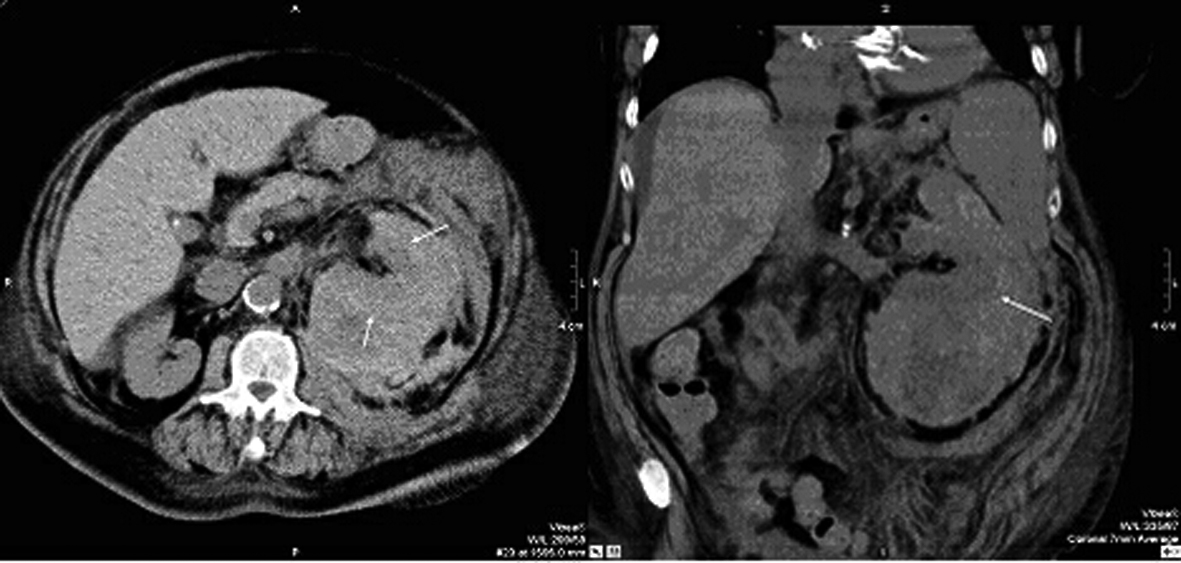

Due to hemodynamic instability coupled with decrease of the haemoglobin value, the third plasma exchange was interrupted prematurely and CT scan was initiated, which revealed an extended inhomogeneous mass around the left kidney which pointed at a combination of parenchymal and subcapsular bleedings. There was also free fluid beneath the spleen and in the lower abdomen (Fig. 1).

![]() Click for large image | Figure 1. Computer tomography of abdomen performed 5 days after renal biopsy: the transversal and coronary sectional image shows the haematoma, the arrows demarcate the kidney. |